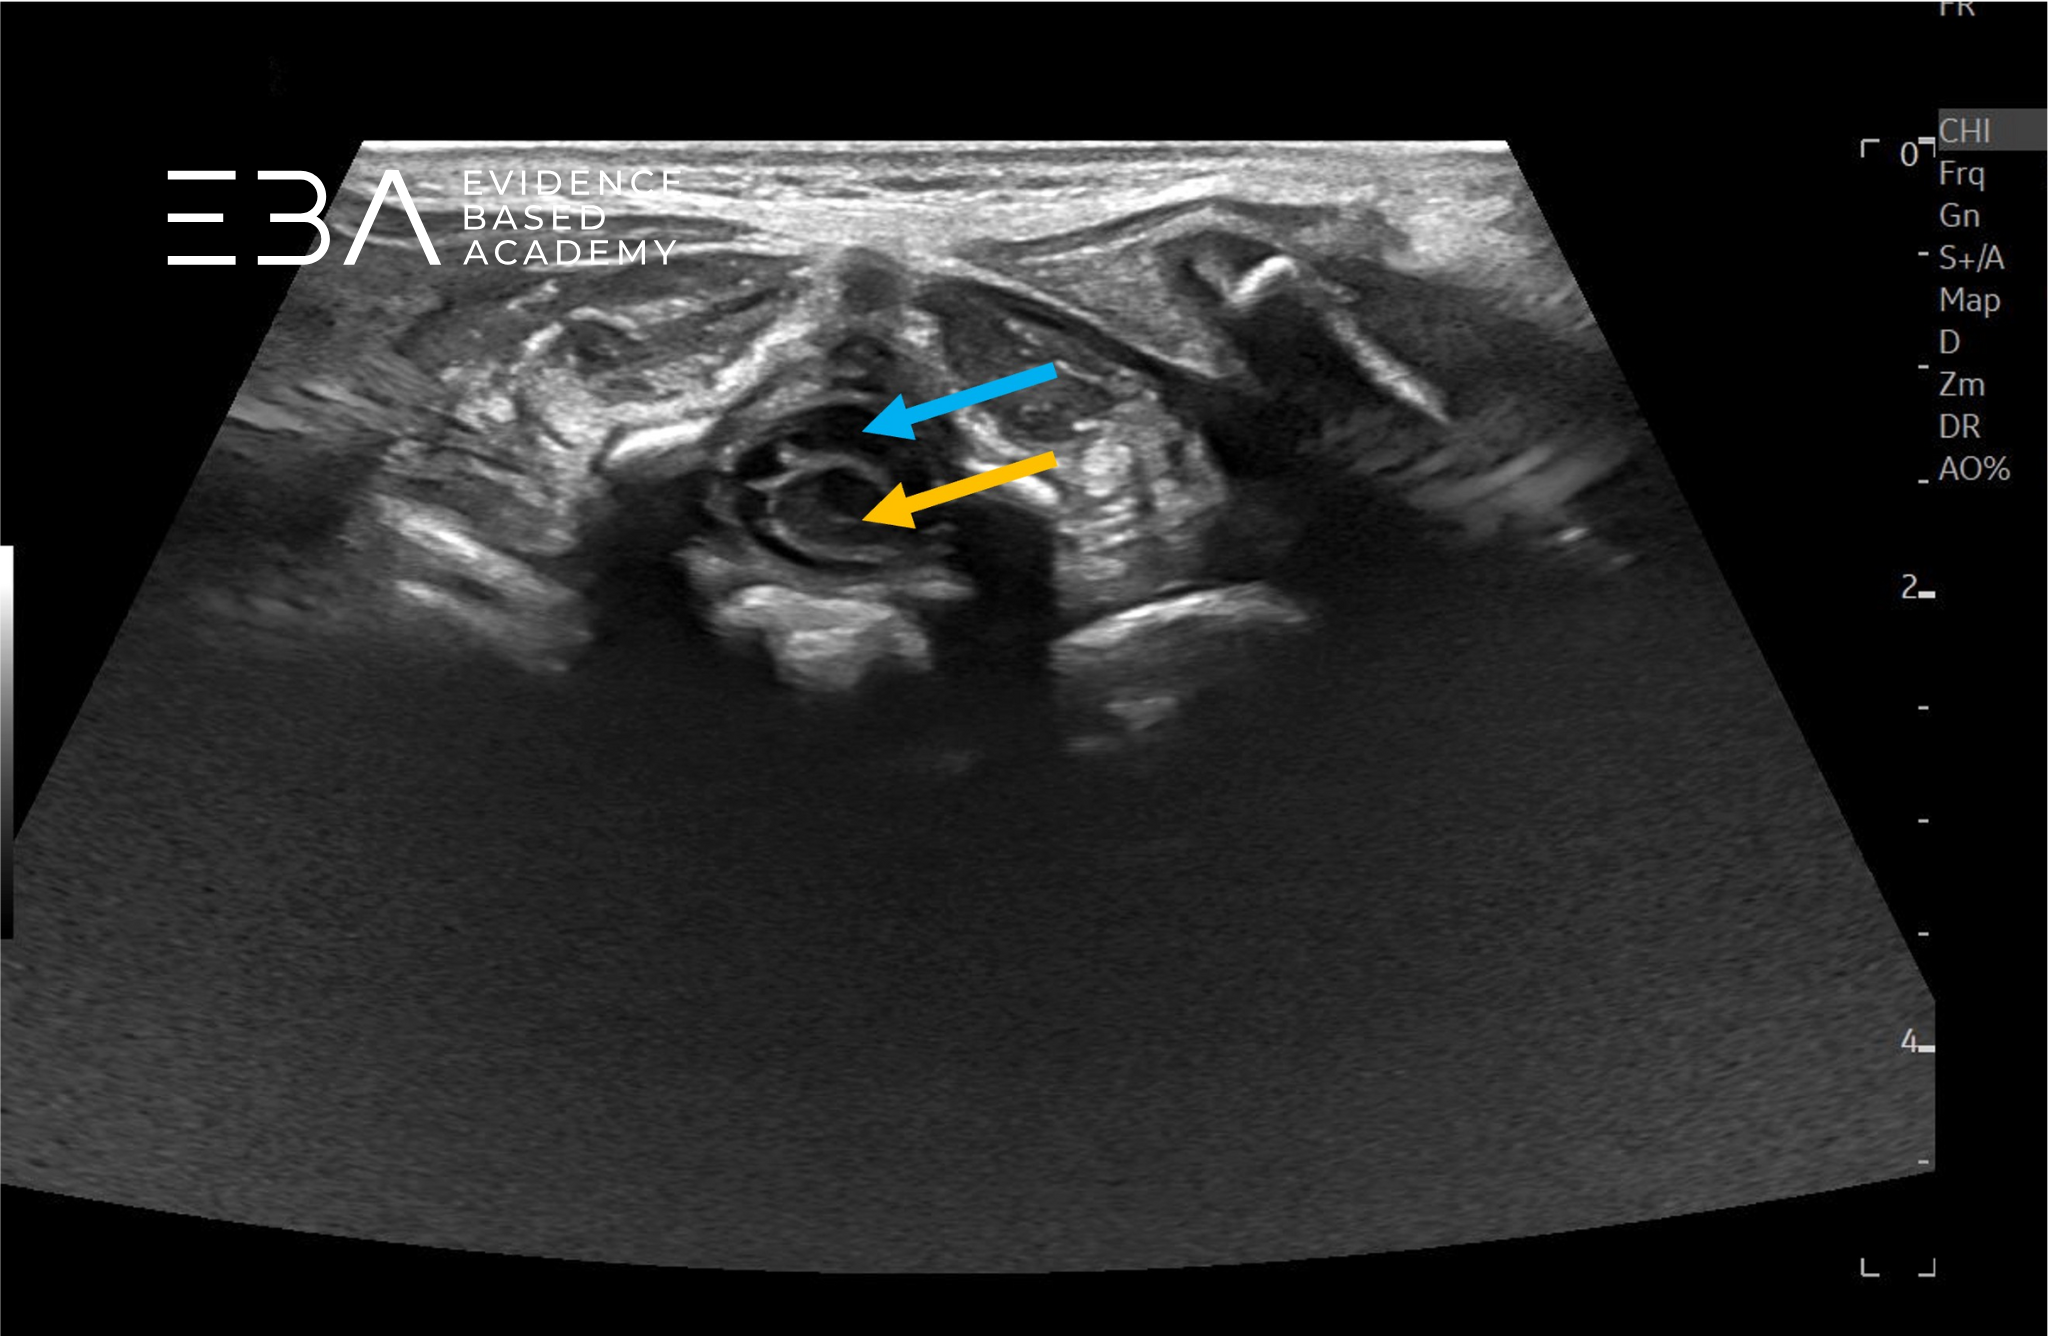

fot. 11

Przekrój podłużny końcowego odcinka kanału kręgowego, numeracja kręgów. Niebieską strzałką zaznaczono koniec worka oponowego.